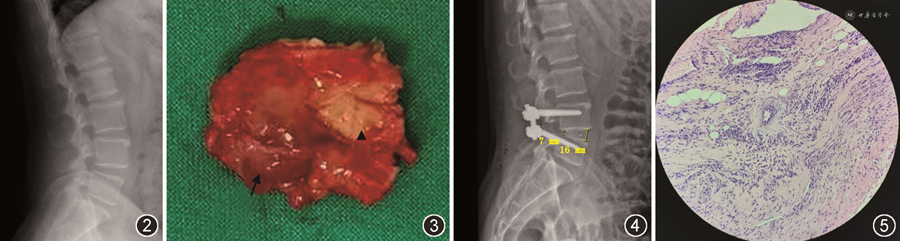

患者男,54岁,以“右下肢麻木、无力2周”为主诉于2021年8月10日入院。患者于2周前无明显诱因出现右下肢疼痛、麻木,以小腿外侧、足背为主,伴右侧足趾背伸无力。查体:双下肢感觉无明显异常,右侧股二头肌、股四头肌、小腿三头肌肌力4级,右侧足拇背伸肌肌力1级,右侧直腿抬高试验50°阳性。腰椎MRI检查显示L4/5椎间隙水平硬脊膜外黄韧带区域类圆形囊性肿物影,边界清楚,位于马尾神经右背外侧,马尾神经明显受压,MRI Tl加权像低信号,T2加权像高信号(图1)。腰椎X线检查提示:腰4椎体向前轻度滑脱、不稳(图2)。诊断“腰椎黄韧带囊肿、腰椎不稳、右侧足下垂”,于全身麻醉下行腰椎后路黄韧带囊肿切除减压融合内固定术,术中在切除病变水平椎板后发现此处黄韧带增厚明显,可见囊肿样病变组织位于黄韧带内,被黄韧带包裹(图3),探查神经根张力较高,进一步行脊柱短缩轴向减压融合内固定术(于L4、L5分别植入一枚合适长度椎弓根螺钉,咬出L4/5棘间韧带及部分骨质,凿除L4下关节突及L5上关节突大部分,扩大L4/5椎间孔,切开L4/5间隙后方纤维环,清除椎间盘组织,连接棒连接双侧螺钉并螺帽固定,椎间隙依次加压,然后锁紧螺帽,图4)。术后病理检查示:镜下见退变变性纤维组织增生,周围血管扩张充血,伴大量浆细胞浸润。病理学诊断为黄韧带囊肿(图5)。术后患者右下肢疼痛、麻木明显缓解,右侧足拇背伸肌肌力3级,随访3个月,症状完全消失,无腰腿痛及下肢麻木等不适,右侧足拇背伸肌肌力4+级。

椎管内滑膜囊肿(SSC)指起源于关节突关节囊形成的囊肿,囊内充满浆液性或胶冻样液,并与关节囊相沟通,可见于脊柱的任何部位,主要发生于下腰椎。Chebib等[1]根据病理改变将SSC分为三类:真性滑液囊肿、黄韧带退变性假性囊肿、腱鞘囊肿。脊柱黄韧带囊肿作为SSC的一种亚型,是椎管狭窄的一个罕见原因,多见于活动度大且退变严重的节段,比如L4/5节段[1]。Wildi等[2]报道了33例腰椎黄韧带囊肿,25例位于L4/5节段,15例合并有腰椎滑脱。Bruder等[3]和Ramhmdani等[4]报道的腰椎滑脱与SSC合并存在的发生率分别为23.0%和42.5%。黄韧带囊肿目前认为与脊柱退变及局部不稳导致的反复微小创伤有关[1,4]。